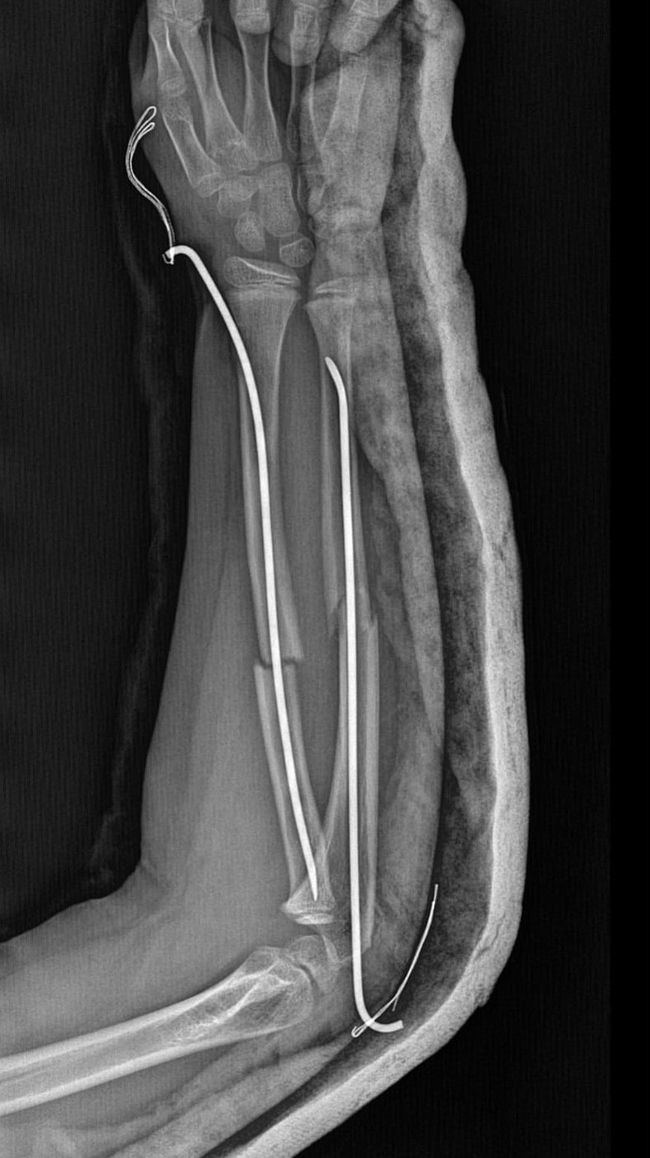

Olay, geçtiğimiz ay Büyükçekmece Tepecik'te bulunan bir ilkokulda meydana geldi. İddiaya göre 8 yaşındaki Y.K.Ş. okulda bir süredir kendisini rahatsız eden 9 yaşındaki çocuk tarafından darp edilerek kolu ikiye katlandı. Y.K.Ş.'nin 2'ye katlanan kolu 2 ayrı yerinden kırıldı. Öğretmenler Y.K.Ş.'nin ailesini arayarak, 'oğlunuz arkadaşıyla kavga etti duvara çarptı' denildi.

Oğlunu okuldan alıp hastaneye götüren anne Songül Gökdemir, oğlunun kolunun 2 ayrı yerinden kırıldığını öğrenip ameliyata alınacağını duyduğunda büyük şok yaşadı. Konuyla ilgili anne Gökdemir savcılığa giderek şikayetçi oldu. Savcılıktan ise 'söz konusu Suça Sürüklenen Çocuğun yaşının 12'den küçük olduğu gerekçesi ile kovuşturmaya yer yoktur' kararı çıktı. Anne Gökdemir karara itiraz ederken mağdur Y.K.Ş. ise haftalardır okula gidemiyor. Eğitimi aksayan çocuğun 2 hafta sonra ise platinlerinin çıkarılması için yeniden ameliyata gireceği öğrenildi.

Kendi imkanımla hastaneye götürdüm. Okula gittiğimde de oğlum derste oturuyordu. Öğretmen ders işliyordu ambulans çağırılmamış. Hastanede kolunda 2 tane kırık olduğunu acilen de ameliyata girmesi gerektiğini öğrendim. 3 gün sonra ameliyata alındı. Kolundaki platinlerden dolayı her gün pansumanı var. 2 hafta sonra tekrar ameliyatı var" dedi.